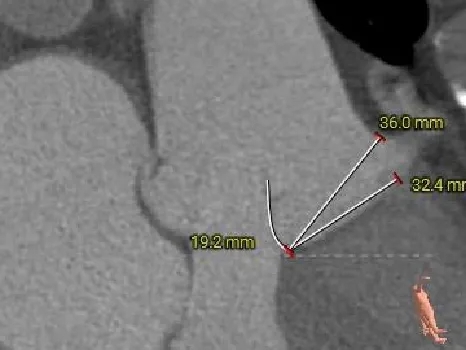

术前CT分析

主动脉根部测量

Annulus 27.2mm

LVOT:26.5mm

钙化积分:0

SOV

52.3*54.9*52.1mm

STJ:45mm

AAO:48mm

纯反流三叶瓣,瓣环内径27.2mm

流出道近直筒型

瓣叶无增厚、无钙化

瓦氏窦、STJ、升主明显扩张

瓣上结构测量

瓣上2mm

28.5mm

瓣上4mm

29.9mm

瓣上6mm

30.9mm

瓣上8mm

33.7mm

瓣上10mm

35.2mm

瓣上12mm

36.3mm

瓣上空间逐渐增大,仅瓣上2mm左右可提供锚定